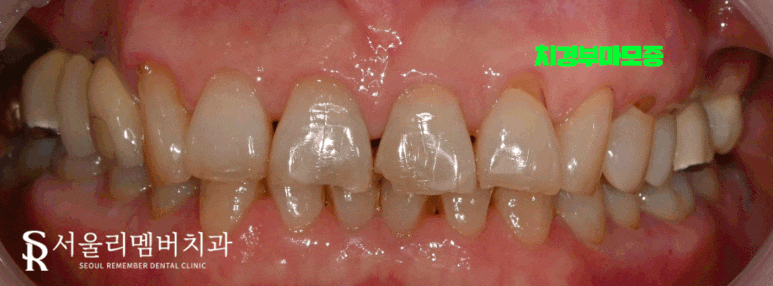

어느 때와 마찬가지로 환자의 구내를 육안으로 확인했는데요.

딱 보자마자 이런 증상을 느끼게 된 이유를 알 수 있었습니다.

앞서 말했듯이 건강한 치은은 치경부를 감싼 채,

탱탱하게 올라와 있는 모습을 나타내는데요.

이 환자의 구강을 딱 보았을 때

겉으로 드러난 치경부가 눈에 띄었습니다.

전치부에만 국한된 문제가 아닌,

전체 치아에서 관찰되고 있었는데요.

특히 임플란트를 올려놨던 치아 주변에서 심하게 나타났습니다.

치주 질환이 진행되어 치은이 밑으로 꺼지게 된 거죠.

그로 인해 벌어진 틈 사이로 음식 찌꺼기들이 끼게 되었으며

통증(식편압입, food impaction)까지 이어진 것입니다.